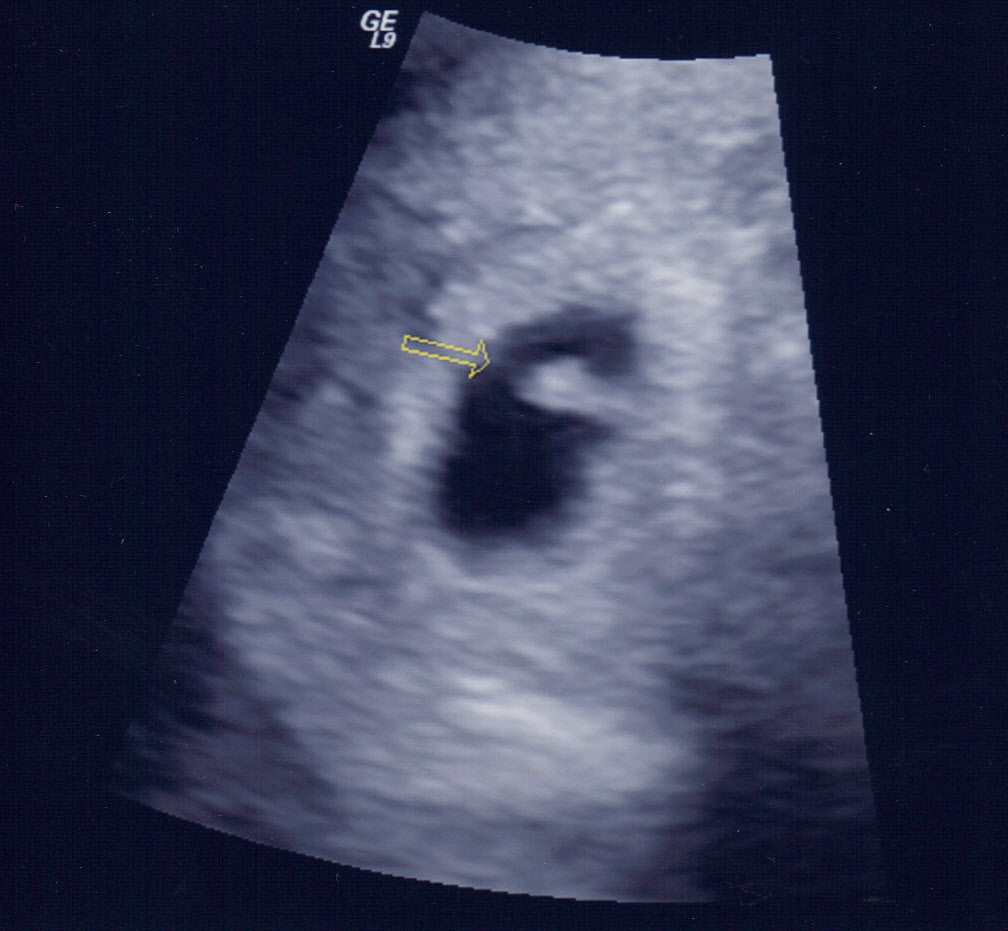

I just had my first US today, how amazing to hear the heartbeat at only 6 weeks! Good strong beat at 105.   Baby measuring at 0.3 cm, which makes it hard to believe how tiny that heart is.  My levels are good, and they estimated me to be due April 21, 2014.  Happy Easter to us!

7/24 Beta 1 150 7/26 Beta 2 313 7/30 Beta 3 1,084 Beta 4 3,000 Beta 5 8,120 1st U/S 8/8 image